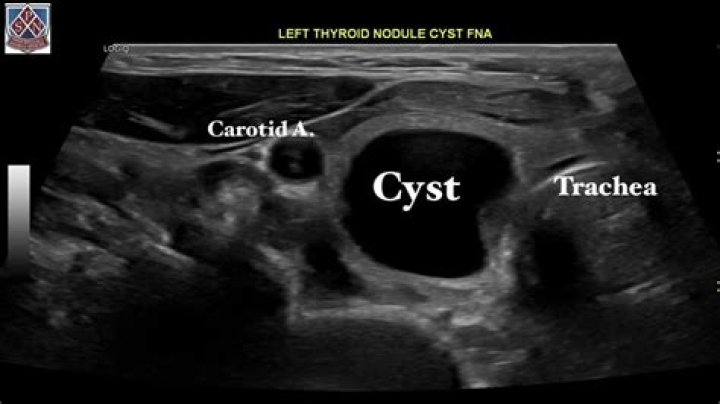

How serious is a cyst on your thyroid?

Thyroid nodules are solid or fluid-filled lumps that form within your thyroid, a small gland located at the base of your neck, just above your breastbone. Most thyroid nodules aren’t serious and don’t cause symptoms.

Thyroid nodules are very common, especially in the U.S. In fact, experts estimate that about half of Americans will have one by the time they’re 60 years old. Some are solid, and some are fluid-filled cysts. Others are mixed. Because many thyroid nodules don’t have symptoms, people may not even know they’re there.

Thyroid cysts: These are growths that are filled with fluid or partly solid and partly filled with fluid. Inflammatory nodules: These nodules develop as a result of chronic (long-term) inflammation (swelling) of the thyroid gland. These growths may or may not cause pain.